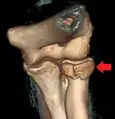

CT scan showing a radial head fracture

Radial head fracture seen on 3D CT reconstruction